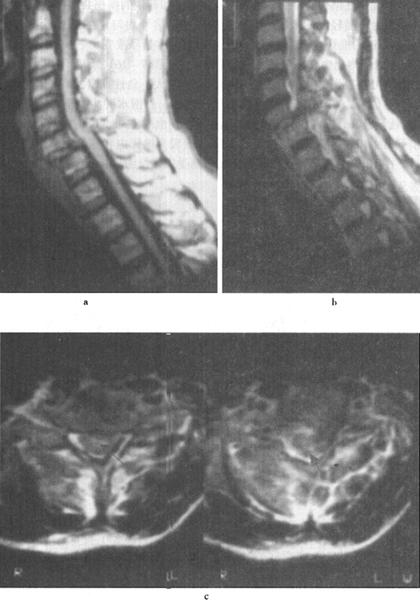

图7-16 L1压缩骨折,脊髓挫裂伤:T1W(a)和T2W(b)矢状面,L1椎体呈楔状变形,椎体骨折,但无移位。后方硬膜外及脊髓内可见高信号血肿,在横断位T1W(c)、T2W(d)成像,如箭头所示脊髓圆锥内椭圆型高信号影,为出血所致。椎体骨髓水肿及出血。